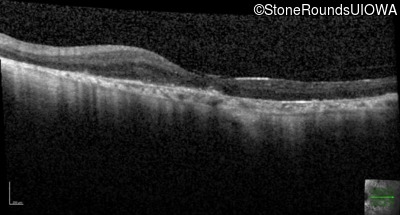

Age at visit: 62 years